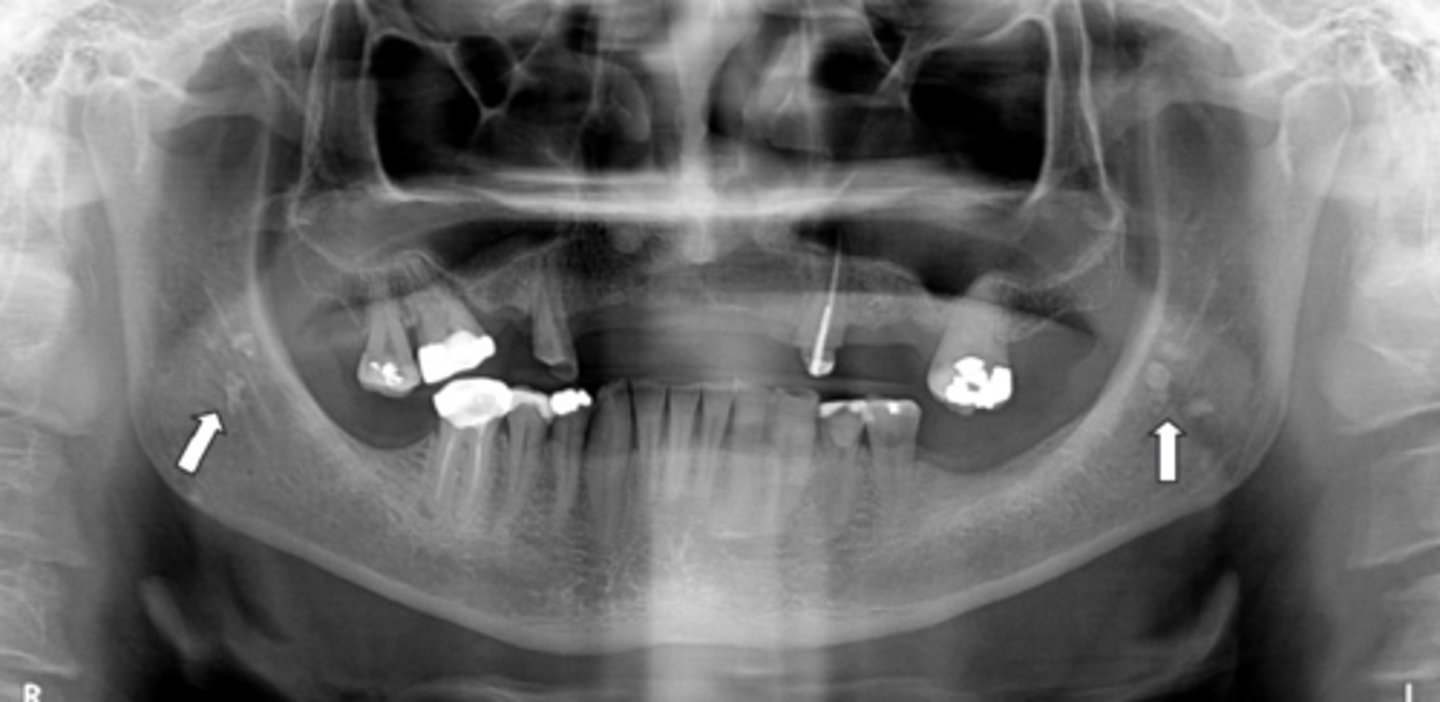

Diffuse sclerosing is seen in which condition?

Florid Osseous Dysplasia

What happens to the inferior border of the mandible in diffuse sclerosing?

Thinned

What is the demographic affected by Cemento-osseous Dysplasia?

AA/Asian women

What teeth does Cemento-osseous Dysplasia affect?

Mandible and maxilla, anterior teeth

What distinguishes the Florid type of Cemento-osseous Dysplasia?

>2 quadrants affected